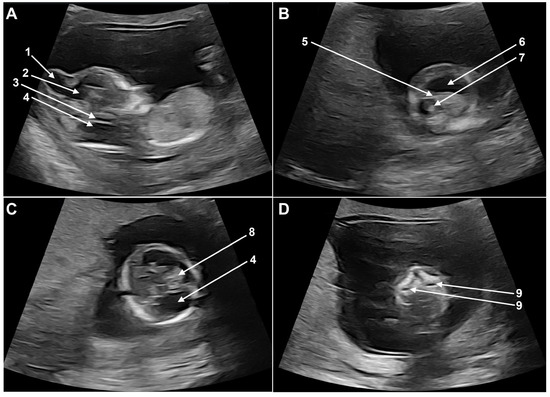

Fetal ultrasound examination at the time of first-trimester scan revealed a severely disrupted cerebral and cerebellar development. The most striking anomaly was the presence of a large cranial encephalocele communicating with the right lateral ventricle (Figure 1A). The cerebral symmetry was disrupted, the left lateral ventricle was dilated, the thalamic area was hypoplastic, and the choroid plexus was small and shifted cranially and anteriorly (Figure 1B,C). The posterior fossa was missing the normal landmarks: the brain stem was hypoplastic, the fourth ventricle (intracranial translucency) could not be identified, the brain stem skull distance was severely enlarged, and the structures of the posterior fossa were replaced by a sonolucent area (Figure 1A,C). The maxillary cavities were prominent, unusual for this gestational age, and bilateral cleft palate could not be excluded (Figure 1D). No further anomalies of the fetus were identified.

Figure 1. Fetal ultrasound images at the time of the first-trimester scan: (A) 1 + 2: cranial encephalocele and communication to right ventricle; 3: hypoplastic brain stem; 4: enlarged posterior fossa. (B) 5: asymmetric cerebral midline; 6: dilated left lateral ventricle; 7: right ventricle. (C) 8: choroid plexus; 4: enlarged posterior fossa. (D) 9: prominent maxillary cavities.